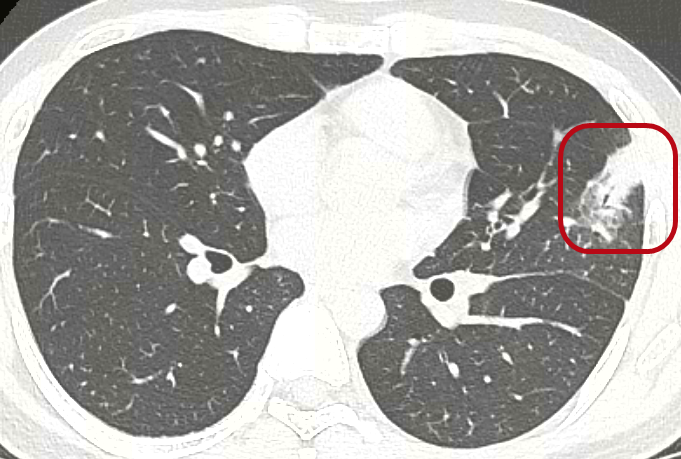

早上7點23分,小林掛上了急診號。半小時內,急診科醫護高效完成接診、打退燒針、抽血及胸部CT等診療。CT初步報告結果顯示,左肺上葉感染。

第二天,小林入院後進一步檢查的結果出來了,幾個異常指標引起了感染科醫療團隊的重視:肝功能提示肝細胞受損,血塗片顯示8%的異型淋巴細胞。同時,他的胸部CT結果顯示,有脾臟腫大跡象。這是一系列難以用單純的肺炎解釋的全身反應。